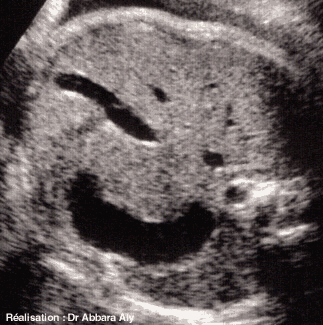

Une coupe abdominale transverse animée, échographique et fœtale

Étude anatomique

Atlas d'échographie